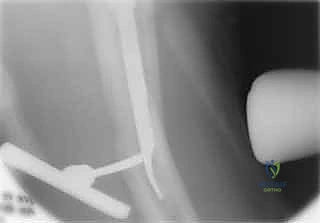

4. توسيع القناة وإدخال المسمار

يتم استخدام أدوات حفر خاصة (Reamers) لتوسيع القناة النخاعية بلطف لتستوعب المسمار المصنوع من التيتانيوم. بعد ذلك، يتم انزلاق المسمار النخاعي الرئيسي داخل العظم حتى يصل إلى العمق المطلوب.

5. تثبيت عنق ورأس الفخذ (المسمار الرأسي)

من خلال ذراع توجيه متصلة بالمسمار الرئيسي، يتم إحداث ثقب في عنق ورأس عظمة الفخذ. يتم إدخال المسمار الرأسي (Cephalic Screw) السميك ليمسك برأس الفخذ بقوة ويسحبه نحو المسمار الرئيسي، مما يضغط الكسر (Compression) ويحفز التئام العظام بسرعة.